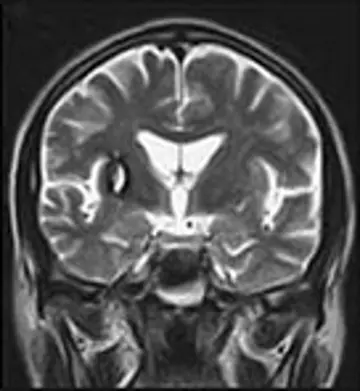

مغز و اعصاب - صفحه 15